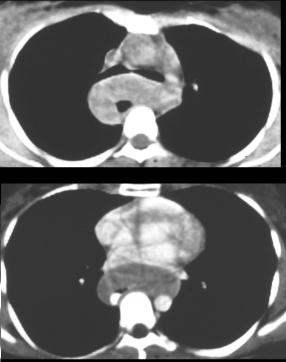

7 Lipomes

: Tumeur de type sous muqueses

,siegent le plus souvent sur oesophage cervicale et

avai aspect de polyp endoluminale . La TOGD se donne image

lacune intra oesophagien , Le CT scanner donne de image de

densite negatif . En IRM le signal est egalement

specifique de graisse .

Image en lacule intra

oesophagien : TOGD de oesophage |

Lipome oesophagien : IRM en coupe

axiale |